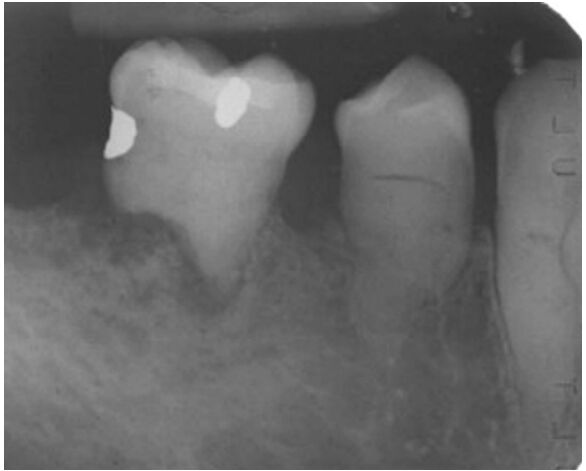

73.附圖之下顎後牙區之根尖片影像,最可能之牙齒變異(tooth anomaly)為何?

(A)缺牙(missing tooth) (B)牛型臼齒(taurodontism) (C)牙本質發育不全(dentinogenesis imperfecta) (D)牙釉質發育不全(amelogenesis imperfecta)